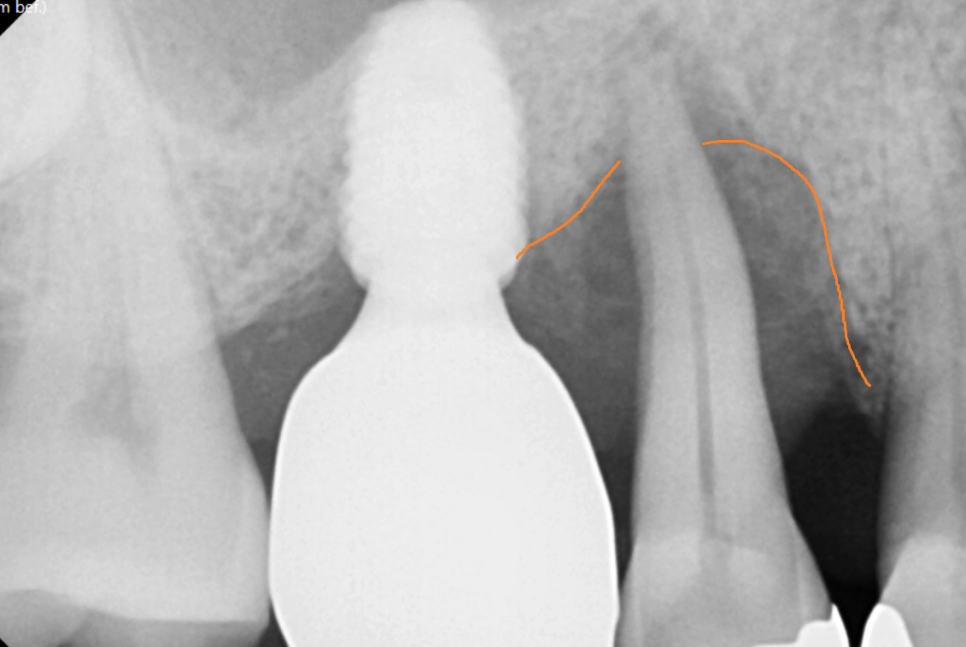

유독 안좋은 부위를

작은 x-ray를 찍어 추가 검사해보았더니..

오른쪽 윗 어금니 치아

잇몸 내려감이 관찰되었습니다.

정확하게 말해서는 잇몸 뼈가 내려간거죠

잇몸 내려감으로 뼈 손실이 심하여

뼈이식을 진행하였는데요